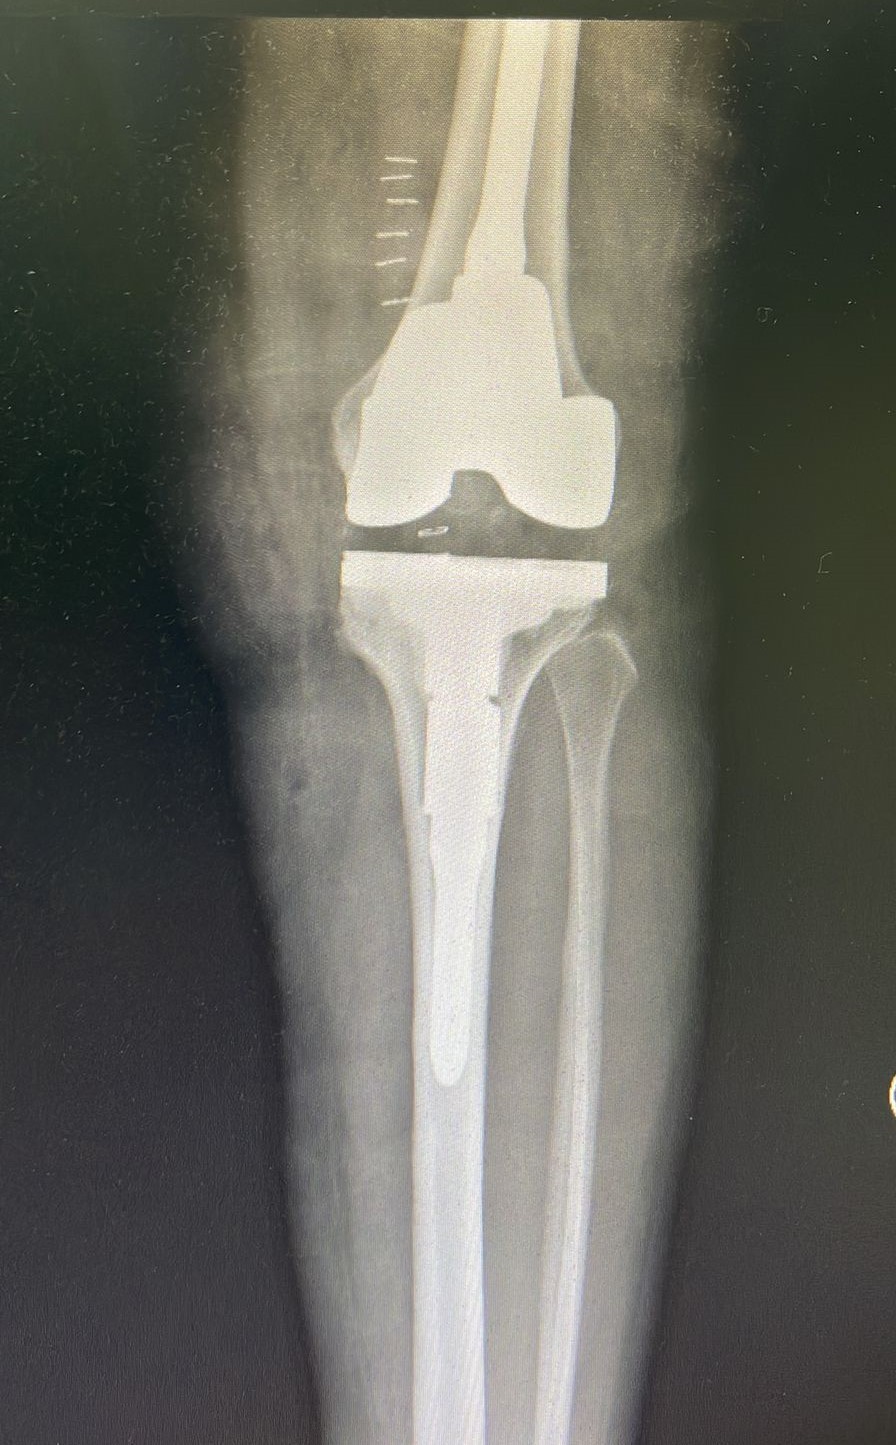

في إنجاز طبي جديد نجح تدخل جراحي نوعي دقيق أجراه فريق طبي متخصص بأمراض وجراحة المفاصل والعظام في مستشفى الملك فهد التخصصي ببريدة باستبدال مفصلي الركبة لمريضة تبلغ من العمر 65 عاماً، واستعادة قدرتها على الوقوف والمشي بقدميها بعد أن كانت تعتمد على الكرسي المتحرك.

وكشف تجمع القصيم الصحي أن المريضة كانت تعاني من احتكاك شديد بالركبتين وتقوس بالأطراف السفلية، بالإضافة إلى تشوهات عظمية مما أدى لصعوبة الحركة لديها وعدم قدرتها على المشي لمسافات متوسطة وطويلة، وبناءً على وضعها الصحي وبعد الاطلاع على نتائج الأشعة المقطعية وعمل الفحوصات والكشوفات الطبية اللازمة قرر الفريق الطبي إجراء تدخل جراحي لها وتبديل مفاصل الركبة.

وأوضح التجمع أن العملية الجراحية أُجريت للمريضة عبر فريق متخصص بهذا النوع من العمليات التي تنفّذ للمرة الأولى في منطقة القصيم، وتم خلالها استبدال المفصلين بمفاصل ثانوية وتعزيزها بزرعات معدنية نخاعية في عظمتي الساق والفخذ مع تعديل التقوس الحاصل في الأطراف السفلية وإزالة التشوهات العظمية.